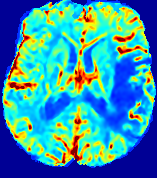

LesionRefer to captionRefer to captionRefer to captionRefer to captionRefer to captionRefer to caption𝐕rgbsubscript𝐕𝑟𝑔𝑏{\bf{V}}_{rgb}Refer to captionRefer to captionRefer to captionRefer to captionRefer to captionRefer to caption𝐕2subscriptnorm𝐕2{\|\bf{V}}\|_{2}Refer to captionRefer to captionRefer to captionRefer to captionRefer to captionRefer to captionRefer to caption3.53.53.52.82.82.82.12.12.11.41.41.40.70.70.70.00.00.0(mm/s)𝑚𝑚𝑠(mm/s)D𝐷DRefer to captionRefer to captionRefer to captionRefer to captionRefer to captionRefer to captionRefer to caption0.0200.0200.0200.0160.0160.0160.0120.0120.0120.0080.0080.0080.0040.0040.0040.0000.0000.000(mm2/s)𝑚superscript𝑚2𝑠(mm^{2}/s)Slice #1Slice #2Slice #3Slice #4Slice #5Slice #6

Figure 3: PIANO feature maps for one stroke patient, where the lesion is located in the left hemisphere. Top row: segmented stroke lesion region (white) on different slices, obtained from ISLES 2017. The corresponding slices for the PIANO feature maps are shown in the following rows.

For a better insight into an estimated velocity field 𝐕𝐕{\bf{V}} and diffusion field 𝐃𝐃{\bf{D}}, we compute the following maps: (1) 𝐕rgbsubscript𝐕𝑟𝑔𝑏{\bf{V}}_{rgb}: Color-coded orientation map of 𝐕=(Vx,Vy,Vz)T𝐕superscriptsuperscript𝑉𝑥superscript𝑉𝑦superscript𝑉𝑧𝑇{\bf{V}}=(V^{x},V^{y},V^{z})^{T}, obtained by normalizing 𝐕𝐕{\bf{V}} to unit length and mapping its 3 components to red, green, blue respectively; (2) 𝐕2subscriptnorm𝐕2\|{\bf{V}}\|_{2}: 222 norm of 𝐕𝐕{\bf{V}}; (3) D𝐷D: scalar field in Eq. 5.

Fig. 3 and Fig. 4 show the PIANO feature maps estimated from two ISLES 2017 patients: all are highly consistent with the lesion in both cases. Details of the blood flow trajectories are revealed in 𝐕rgbsubscript𝐕𝑟𝑔𝑏{\bf{V}}_{rgb} by the ridged patterns and the sharp changes of colors in the unaffected (right) hemisphere, while the flat patterns appearing within the lesion provide little directional information about the velocity and indicate low velocity magnitudes. Velocity magnitudes are more directly visualized via 𝐕2subscriptnorm𝐕2\|{\bf{V}}\|_{2}, from which one can easily locate the lesion where 𝐕2subscriptnorm𝐕2\|{\bf{V}}\|_{2} is low. D𝐷D also indicates lower diffusion values in the lesion, though with less contrast potentially due to the fact that it captures the accumulated effect of CA diffusion at the voxel-level.